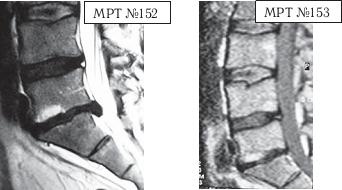

На МРТ № 154 наблюдается состояние поясничного отдела позвоночника после двух операций в сегментах LIII-LIV и LV-SI секвестрированная грыжа межпозвонкового диска в сегменте LIV-LV, абсолютный стеноз спинномозгового канала. На МРТ № 155 — состояние поясничного отдела позвоночника после лечения методом вертеброревитологии. А в этом случае пациента привезли в клинику с целым «букетом» заболеваний позвоночника. ![]() На МРТ № 156 наблюдается состояние поясничного отдела позвоночника после операций: рецидив грыжи межпозвонкового диска в сегменте LIV-LV, абсолютный стеноз спинномозгового канала на этом уровне, спондилёз, эпидурит, арахноидит, наблюдается грыжа межпозвонкового диска в сегменте LV—SI. На МРТ № 157 — состояние поясничного отдела позвоночника после лечения методом вертеброревитологии. Обратите внимание на процессы репаративной регенерации в межпозвонковых дисках в сегментах LIV-LV и LV-SI после лечения данным методом. Следующий случай также по-своему уникален. Это ещё одно прямое свидетельство широкого спектра возможностей вертеброревитологии в решении задач, многие из которых на современном этапе медицины считались неразрешимыми.